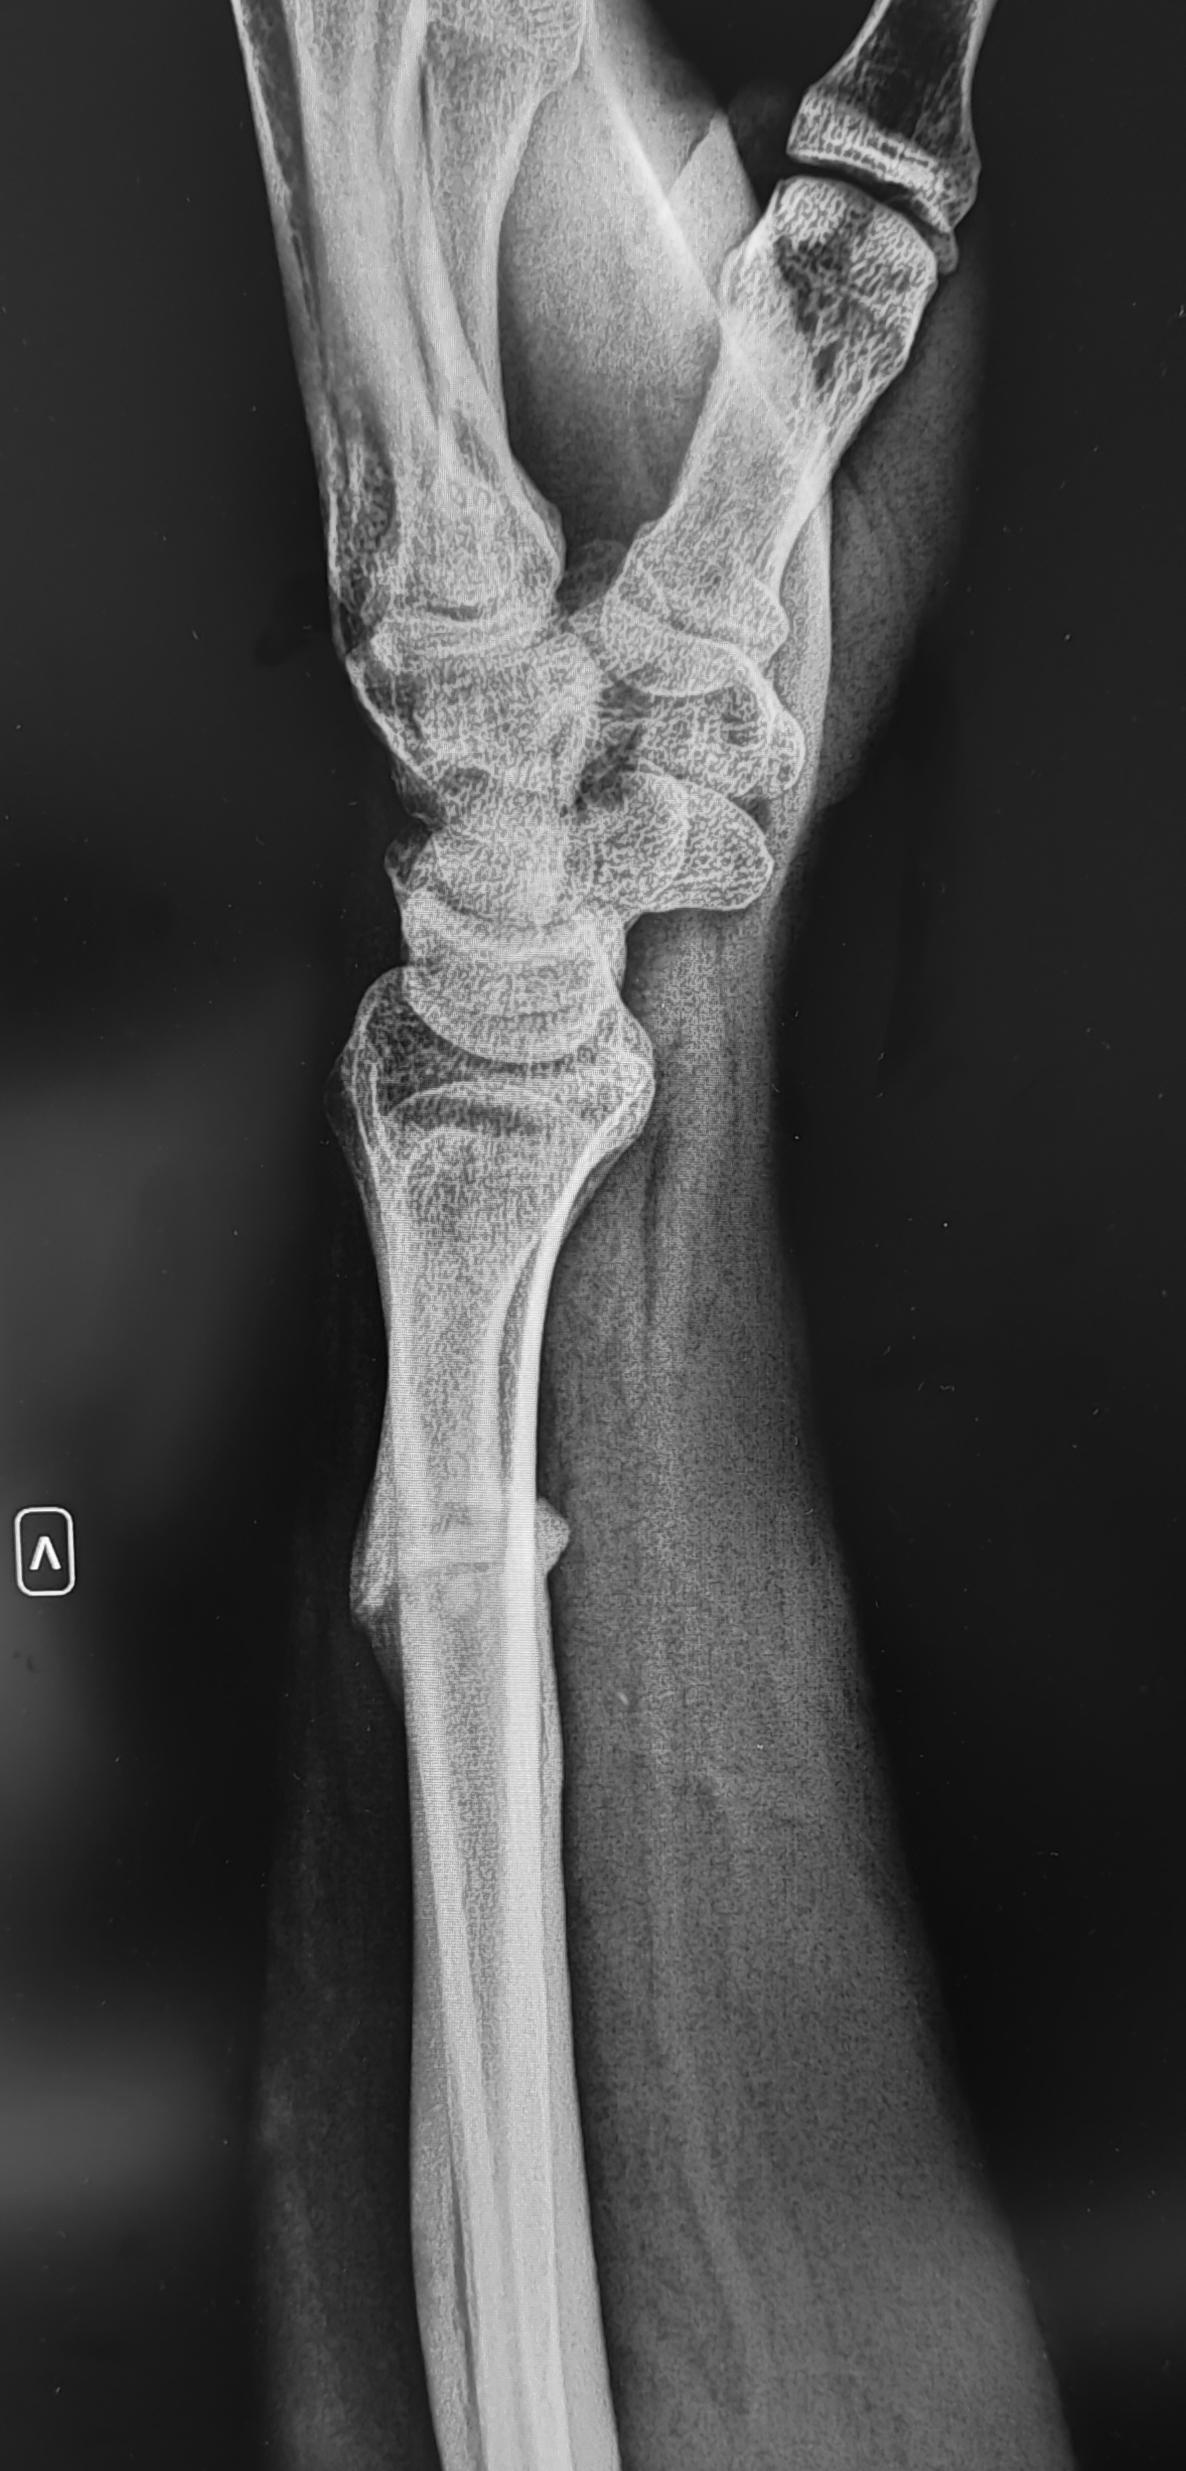

Визуализируется горизонтальная линия просветления в дистальной трети диафиза левой локтевой кости(перелом),выраженное разрастание периостальной костной мозоли вокруг линии перелома, ось кости сохранена, контуры отломков локтевой кости склерозированы. Заключение: Ложный сустав(псевдоартроз) левой локтевой кости.